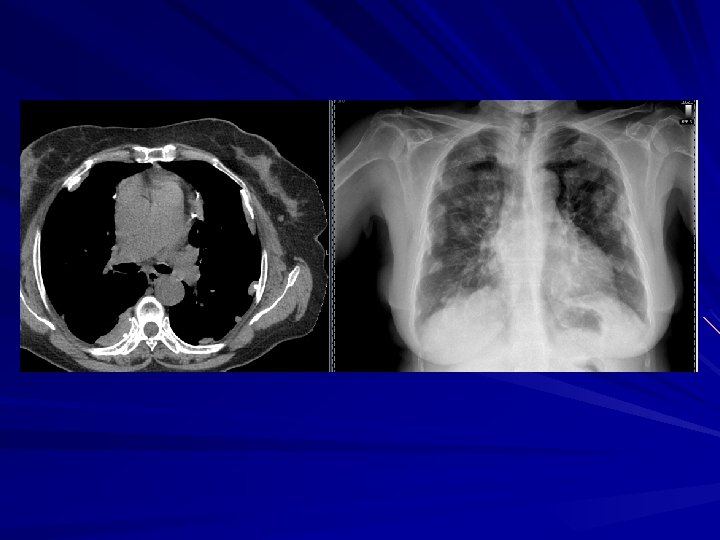

Görüntüleme yöntemleri Akciğer grafileri – İki yönlü akciğer grafisi (ayakta) – Yatarak akciğer grafisi – Yan dekübitüs akciğer grafisi Ultrasonografi Bilgisayarlı tomografi Manyetik rezonans görüntüleme

Ayakta PA akciğer grafisi Saptayabilmek için gerekli minimum miktar – 175 m. L Bazen 500 m. L sıvı bile görülemeyebilir Bulgular: – – – Diyaframın yükselmiş gibi görünmesi Kostofrenik sinüsün kapanması Menisküs bulgusu Üst kenarı konkav opasite – Masif effüzyon: Opak hemitoraks Mediastenin karşıya itilmesi – Atelektazi varsa olmayabilir

Plevral effüzyon miktarı ve PA grafideki görünüm 175 m. L : sinüs küntleşir – Lateral grafide 75 m. L 500 m. L: diyafram konturunu siler 1000 m. L: 4. kosta ön bölümüne yükselir